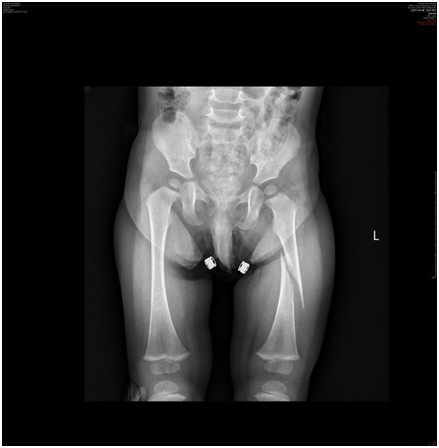

Zdrowy 16-miesięczny chłopiec trafił do izby przyjęć. Rodzice poinformowali lekarza dyżurnego, że dziecko upadło w domu potykając się o niewielką przeszkodę. Lekarz zlecił wykonanie zdjęcia radiologicznego kończyn dolnych (poniżej). Najbardziej prawdopodobną przyczyną urazu jest:

Pytanie 115